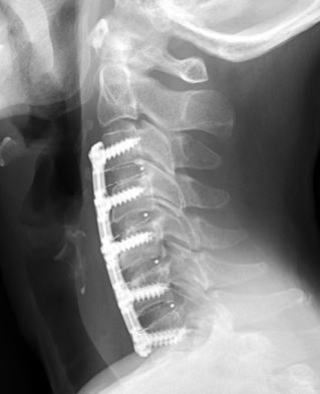

頸椎症(神経根症、頚髄症)の保存的治療、手術療法の選択

頸椎症の手術適応は一ヶ月以上の保存的治療を行っても改善せず日常生活にかなり支障がある、上肢の筋萎縮や麻痺、歩行障害、膀胱直腸障害などが認められるなどに加えて画像診断上痛みと異常所見が合致し手術により改善が見込めることが重要です。頸椎症の神経障害のレベルは慢性に徐々に進行するのではなく、転倒などの頚部の外傷、頚部の運動、頚部の不良な姿勢をとったときなどに悪化し、しばらくすると緩解するといった再発と緩解を繰り返すことが多いとされています。

治療:軽症例は保存治療、重症例~進行性は手術療法。保存治療として装具療法(昼間のみ、夜間は外す。高齢者は転倒防止のため歩行時は外す。)や持続牽引をおこないます。装具は装着して症状が悪化することもあり高さの調整が重要です。持続牽引は軽症例では短期であれば有効な治療となりえます。頚髄症における頚椎間欠牽引療法はエビデンスが無く意義は不明です。持続牽引は入院で行います。持続牽引はグリソン牽引で2-3キロまで、直達牽引であるクラッチフィールドやハローリングでは15kg程度の牽引が限界となっています。

治療は消炎鎮痛剤、中枢性筋弛緩剤、プレガバリンなどの内服薬、外用薬、頚椎の間欠牽引、頚椎装具などを行います。保存療法での治癒率は70%前後とされています。症状の改善しない場合や悪化する場合は手術を考慮しますが、実際にはしびれや痛みよりも筋力低下などの運動神経症状が強くなってくると手術を選択することが多いです。従ってほとんどのケースで手術をすることなく保存療法で対応し、どうしても旨く治らないケース(進行性の筋力低下や保存療法に抵抗する激しい疼痛)のみ手術を選択しますが、おそらく神経根症のうち数%程度ではないかと思われます。

治療

高度の神経麻痺症状がなければ、原則として保存治療を行います。安静、消炎鎮痛剤、頚椎の牽引、温熱治療。慢性期には、ストレッチ、頚部筋力強化訓練、理学療法。保存治療に抵抗性で症状の再燃を繰り返す場合や、筋力低下、脊髄症状を呈する場合は手術が行われます。後方アプローチから椎間孔拡大術が行われる場合が多い。